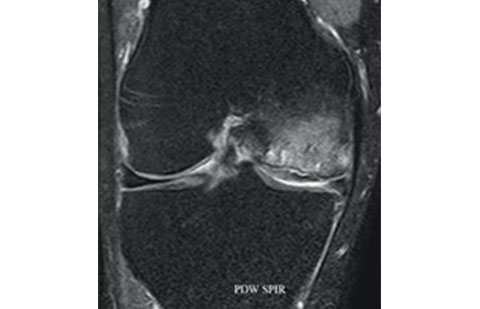

Os exames de imagem são de grande valia para o diagnóstico da fratura por fadiga ou síndrome da insuficiência do joelho. A ressonância é o exame que mais auxilia neste diagnóstico.